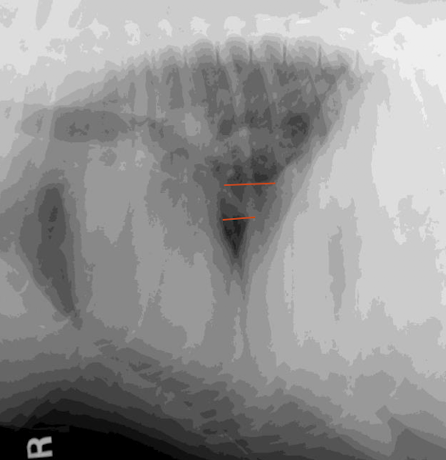

Wha condition is this image depicting? What is the red label showing?

Shoulder DJD

Osteophytes present on the caudal glenoid cavity and caudal humeral head